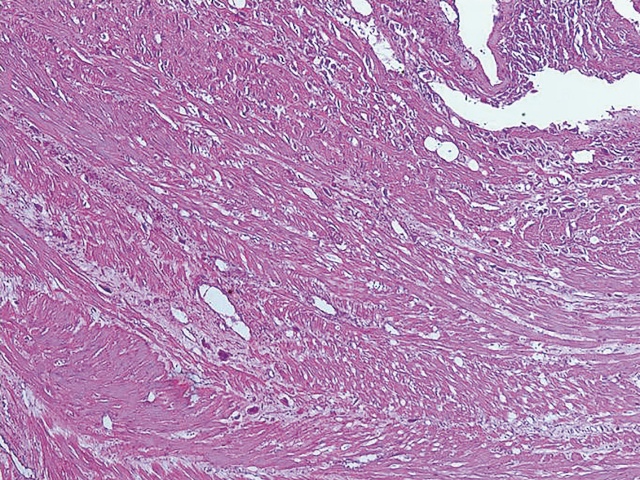

И, в заключение. Несмотря на бесспорный диагностический потенциал выявления PAS описанных выше визуализирующих технологий (УЗИ, МРТ), они не обеспечивают 100% верификацию патологии. Окончательный диагноз устанавливается сначала интраоперационно (рис. 15) и далее только в ходе патологоанатомического исследования (рис. 16-18), помня о том, что клинические и патологоанатомические диагностические стандарты для PAS мало изменились с 1937 г.

Рис. 17. PAS. Микрофотография. Глубокая инвазия клеток синцитиотрофобласта в миометрий. Окраска гематоксилин-эозином. х 50.

Рис. 18. PAS. Микрофотография. В зоне рубца фибриноидный некроз, инвазия клеток трофобласта и ворсин в клетчатку параметрия. Окраска гематоксилин-эозином. х 50.